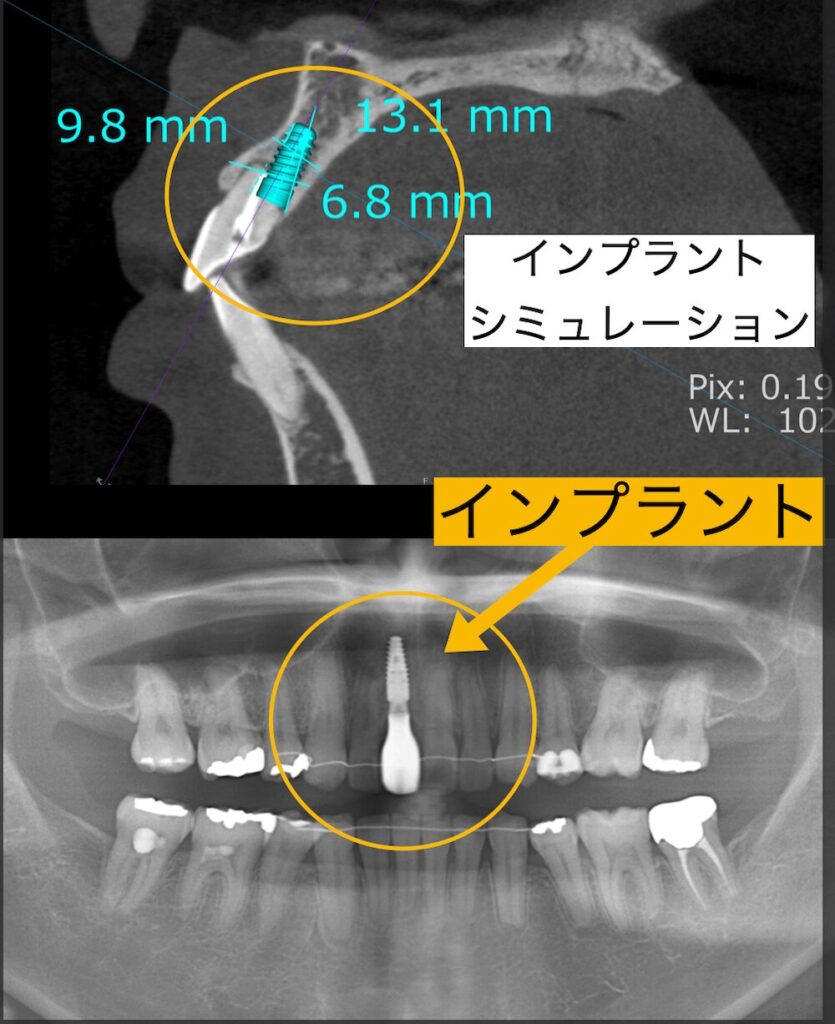

この患者様は学生時代に前歯を強打し、上顎右側中切歯の神経が死んでしまいました。そして、根の先が吸収してしまい、グラグラと動揺していました。両隣の歯は綺麗であり、ブリッジを選択して歯を削るのはもったいない。患者様もできるだけ歯を削りたくないとのことで、インプラント治療を選択されました。審美領域であるインプラント治療は非常に難しく、歯茎の形やボリュームをコントロールする必要があります。治療後は全く天然歯と見分けがつかない被せ物が入り患者様は非常に喜ばれました。

前歯のインプラントの位置は通常の自分の歯根の位置よりも内側に埋入します。これは人工歯根であるインプラントと天然の歯根の生体的特徴と構造上の違いから生じます。それらをしっかりと理解し、シミュレーションを行い、治癒過程を予測してくれる経験豊富なドクターに診てもらいましょう。